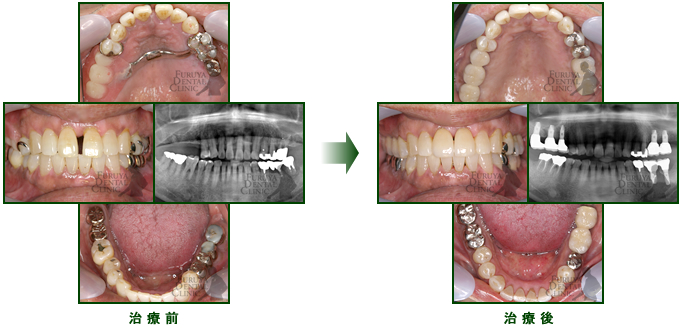

60代 男性

奥歯が入歯ではしっかり噛めないので、インプラントを施術し快適に食事して頂いてます。

前歯のすきっ歯はラミネートベニア法で対応。